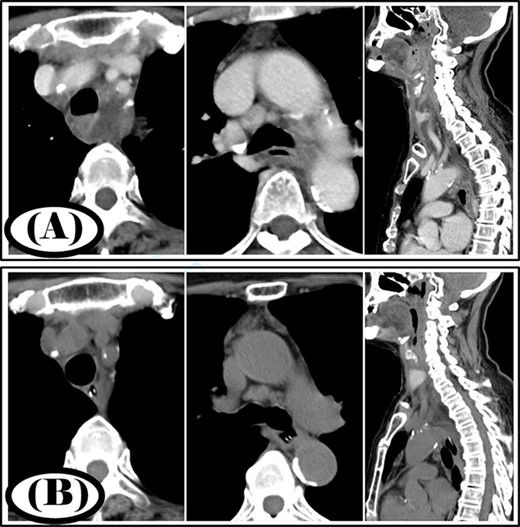

A 68-year-old woman was diagnosed with a posterior pharyngeal abscess triggered by a fever and sore throat. Cervicothoracic CT showed that the infection had spread to the mediastinum (Fig. 3A), and the patient was diagnosed with type IIB DNM. Cervical drainage and mediastinal drainage were performed simultaneously. Mediastinal drainage using only the cervical approach was sufficient. Streptococcus sanguinis was detected in the mediastinal abscess cavity. Continuous irrigation with saline (2 l/day) was initiated immediately post-surgery. The duration of irrigation, drainage and hospital stay were 10, 13 and 22 days, respectively. Four weeks post-surgery, cervicothoracic CT showed no abscess cavity and an improvement in infection was noted (Fig. 3B).

Case 3: pre- and post-treatment cervicothoracic CT; (A) pre-operative cervicothoracic CT and (B) cervicothoracic CT 4 weeks after treatment.